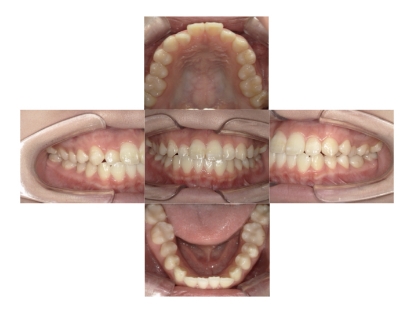

症例2

上下顎前突、叢生

抜歯

ブラケット矯正

上下顎前突、叢生(上下出っ歯、上下の前歯のガタガタ)のケースです。

装置はラビアル(上下表側)で、上下顎の小臼歯を4本抜歯を行っています。抜歯したスペースを使って、上下の前歯の後方移動と叢生(ガタガタ)の改善を行っています。

主訴 前歯のガタガタと口元がでているのが気になる。

年齢・性別 30歳 女性

お住まいの地域 東京都大田区

治療方針 抜歯スペースを利用して上前歯の叢生(ガタガタ)と口元突出の改善

抜歯部位 上下顎左右第一小臼歯

使用装置 ラビアル(上下表側)、顎間ゴム

治療期間 1年11か月

治療回数 13回

リテーナー クリアリテーナー

BEFORE

AFTER